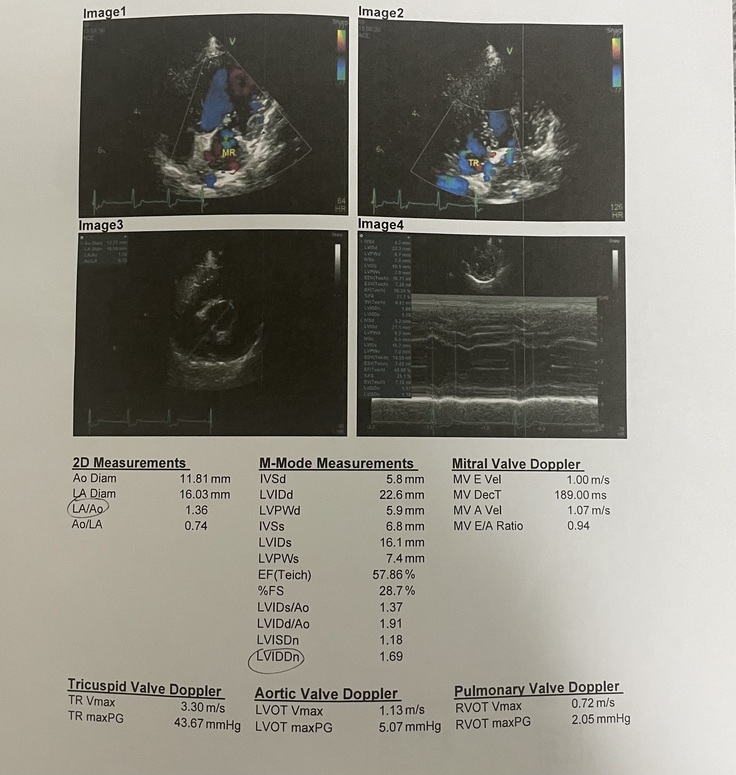

次にエコーですが

青いところが逆流の場所で緑のところが特に血液が乱れているところみたいです。少し逆流が見られますが、これも許容範囲のようです。